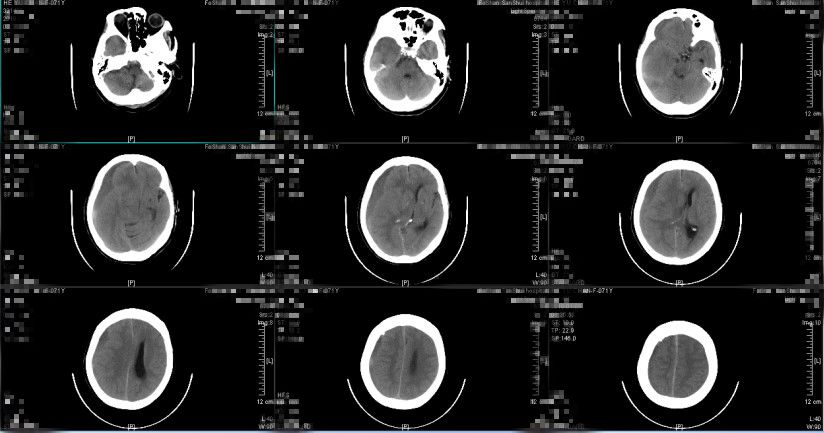

图1. 入院前急诊查头颅CT提示:1.右侧额颞顶部硬膜下血肿,中线略向左移位2.考虑少量蛛网膜下腔出血(2018-12-21 12:53)

患者入院时受伤程度轻,无昏迷,GCS评分15分,提示脑挫伤轻微;入院时头颅CT提示沿硬膜下间隙分布的窄弧带样高密度影,呈断线样高低密度混杂影,中线结构向左偏移约0.5cm,最大血肿厚度约0.8cm,基底池无受压,血肿多位于侧裂附近额顶部,且患者为老年女性,脑萎缩提供了一定的代偿空间,综合考虑此病例为“早期快速自然消散”的特殊类型急性创伤性硬膜下血肿。详细与患者及其家属讲解病情后,采取保守治疗观察方案,密切观察生命体征变化,保持呼吸道通畅,密切观察神经系统体征,给予止血、维持水电解质平衡、控制血压等对症支持处理,未予脱水药物处理,拟伤后12小时再次复查头颅CT检查。

图4. 伤后约10小时复查头颅CT提示:硬膜下血肿较前减少消散,以低密度血肿减少为主,中线结构偏移程度减轻。(2018-12-21 20:16)

患者入院后仍保持清醒状态,头痛等症状无继续加重,根据复查头颅CT检查提示硬膜下血肿较前减少,最大血肿厚度约0.5cm,中线向左偏移约0.3cm,提示此病例为“早期快速自然消散”的特殊类型急性创伤性硬膜下血肿,继续予保守治疗观察。

图5. 入院后第二天复查头颅CT提示:硬膜下血肿继续较前减少消散,中线结构大致居中。(2018-12-22 14:53:08)